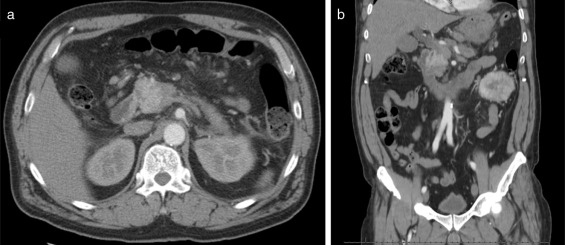

Endoscopic retrograde cholangiopancreatography (Fig. 2 ) revealed dilatation of main biliary duct, and a transendoscopic sphincterotomy and placement of a biliary stent (10 Fr, 9 cm) were performed. Abdominal magnetic resonance (MRI) and cholangio-MRI described the pancreatic lesion as discretely hypointense on T1 and discretely hyperintense on T2, with enhancement in the early phase after gadolinium injection and gradual attenuation in the later sequences.

Endoscopic retrograde cholangiopancreatography – the obstruction (arrow) and ...

Fig. 2.

Endoscopic retrograde cholangiopancreatography – the obstruction (arrow) and marked dilatation of main bile duct (arrowhead).